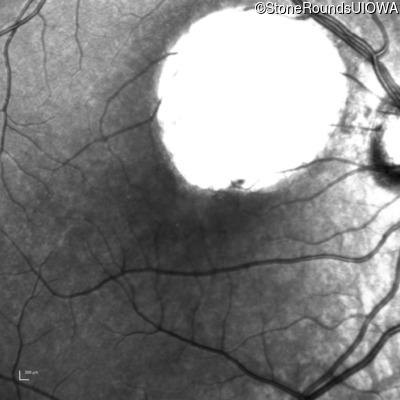

Infrared Fundus Photograph - Left - 20/50 +2

Exemplar